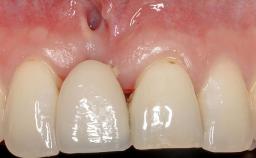

A 30-year-old woman was referred by her general dentist for evaluation of an esthetic complication related to previous implant treatment for congenitally missing maxillary lateral incisors. The patient’s chief complaint was the inadequate esthetic appearance of her smile. The case demonstrates the use of a combined approach to achieve optimal results. Two different flap designs - a tunnel technique and a coronally advanced flap - are employed based on the surgical objectives for the affected site.

Periodontal Plastic Surgery and Prosthetic Procedures to Treat Peri-Implant Soft-Tissue Dehiscences

Lip Line No exposure of papillae Exposure of papillae Full exposure of mucosa margin

Soft Tissue Anatomy Intact Defective